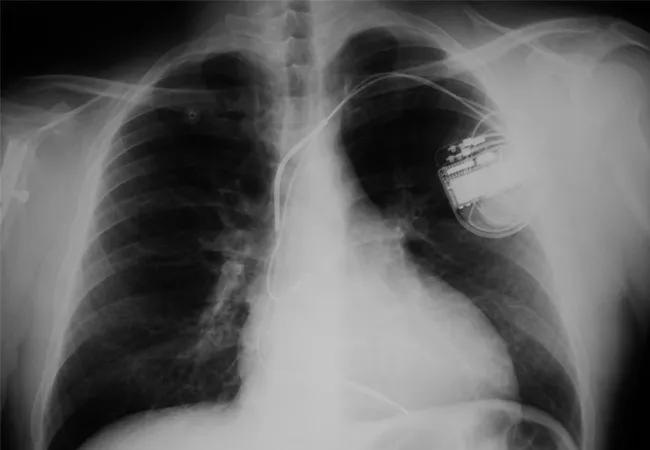

Recent advances in medicine and technology have led to the development of implantable cardioverter-defibrillators (ICDs), which are devices capable of detecting arrhythmias and delivering corrective electric shocks.

In the general population, the benefits of ICDs in preventing sudden cardiac death are now well-proven. Since patients with CKD appear to die more frequently from SCD, the intuitive assumption is that this population would gain significantly from ICDs. Unfortunately, the major studies that established the indications for ICD placement excluded patients with chronic kidney disease, so the benefits in this population remain uncertain.